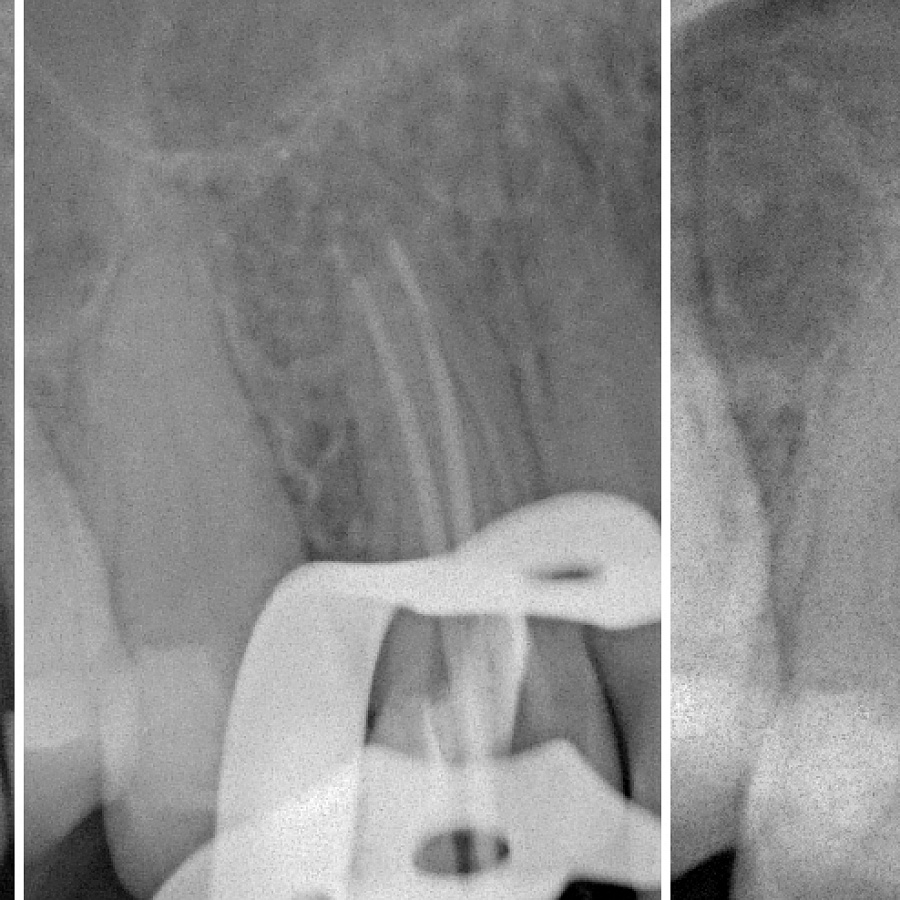

На снимке — щечный канал 14 недопломбирован, периапикальное разряжение костной ткани.

Проведено эндолечение с использованием оперативного микроскопа, небный и щечный каналы обтурированы гуттаперчей с использованием AH-26(д-р Р. Акопов). В это же посещение небный канал подготовлен эндодонтом под литую культевую штифтовую вкладку - гуттаперча извлечена на 2/3 длины канала.

Вкладка изготовлена из золотосодержащего сплава и передана в клинику. После примерки и контрольного R-снимка вкладка зафиксирована в 14 на цемент Relyx U-100. Припасована и зафиксирована на временный цемент временная коронка, изготовленная в лаборатории из Protemp Garant 4.